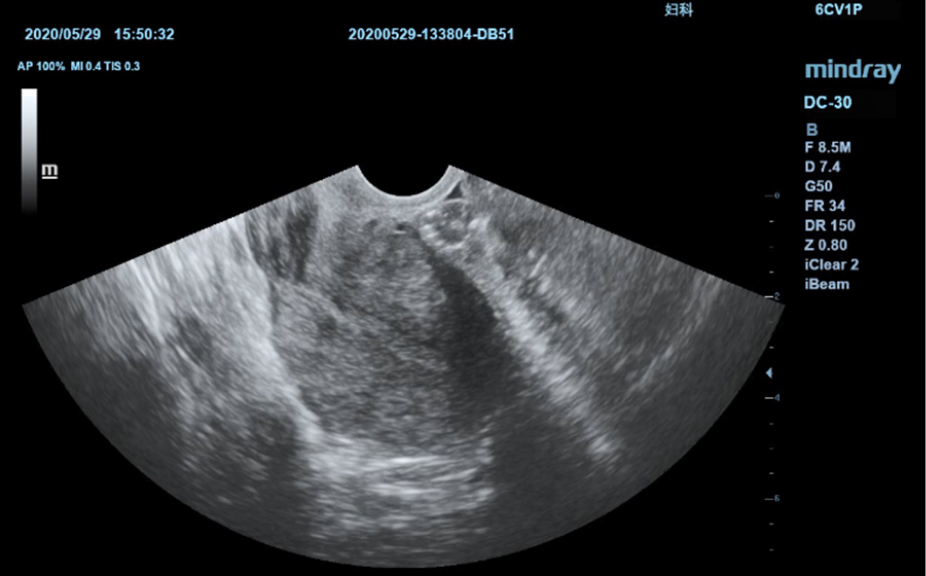

Анатомические иллюстрации, включающие схемы и УЗИ-изображения.

Боковое отображение стандартной эхограммы, обеспечивающее визуальное наведение на изучаемую область.

Стандартные эхоизображения

3

Сравнение результатов сканирования в реальном времени для справки.